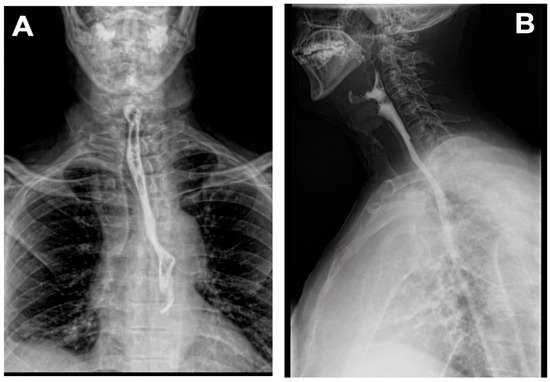

Background: Zenker’s diverticulum arises from the posterior hypopharyngeal wall through Killian’s dehiscence and predominantly affects older adults. Surgical and endoscopic treatments may be complicated by adverse events, including recurrent laryngeal nerve injury, cervical emphysema, mediastinitis, and pharyngoesophageal fistula formation. Methods: We report the case of a 69-year-old male who underwent open surgical treatment for Zenker’s diverticulum and subsequently developed an upper esophageal fistula complicated by a retroesophageal abscess. Results: The patient was treated using an externally adapted endoluminal vacuum-assisted closure system (EndoVAC), which enabled continuous drainage, local lavage, and progressive closure of the esophageal defect. Conclusions: Endo-VAC therapy represents a safe and minimally invasive therapeutic option for the management of postoperative esophageal fistulas following Zenker’s diverticulum surgery and may reduce the need for extensive esophageal reconstruction. Full article

Figure 1